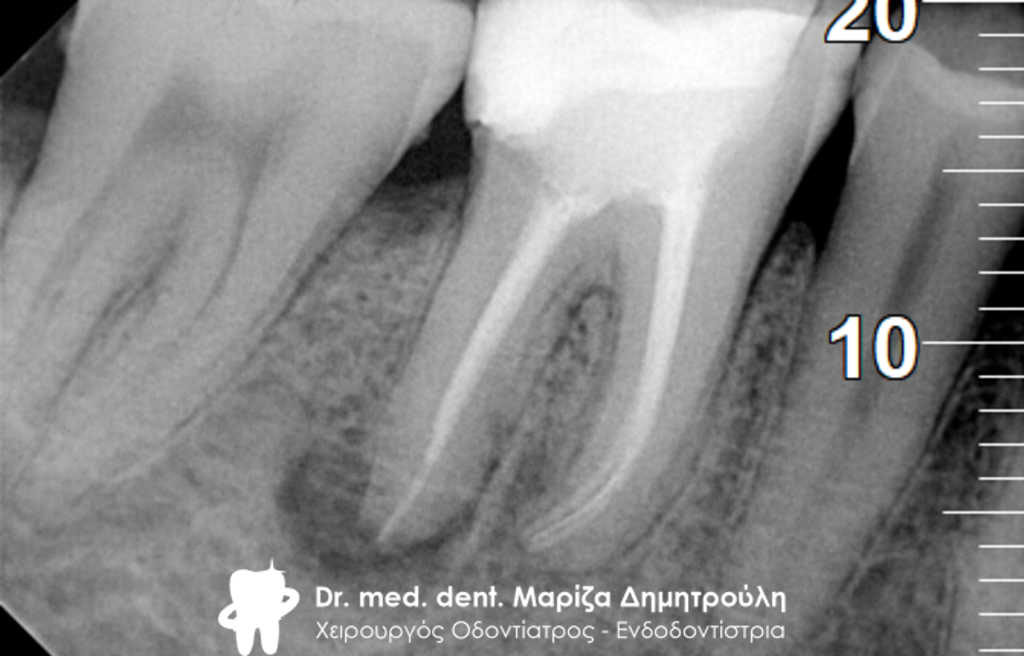

Περιστατικό – Επανάληψη απονεύρωσης και προσθετικής

Η ασθενής παρουσιάστηκε στο ιατρείο με την επιθυμία να ξανακολληθούν οι στεφάνες της στους δυο κάτω αριστερούς προγομφίους, γιατί τον τελευταίο καιρό της αισθανόταν “λίγο χαλαρές”.

Η κλινική εξέταση των δοντιών έδειξε κάτι πιο πολύπλοκο απ΄ αυτό που περιέγραφε η ασθενής. Οι στεφάνες ήταν πράγματι χαλαρές και δεν προσάρμοζαν πάνω στα δόντια, γιατί τα δόντια κάτω από τις στεφάνες είχαν επανατερηδονιστεί.

Η ακτινογραφική εξέταση αποκάλυψε ότι και τα δύο δόντια είχαν απονευρωθεί στο παρελθόν, έφεραν το καθένα στο εσωτερικό χυτό μεταλλικό άξονα και στο ακρορρίζιο διαπιστώθηκε μια περιακρορριζική αλλοίωση. Η αλλοίωση αυτή μαρτυρά τη φλεγμονή του δοντιού στο άκρο της ρίζας.

Μετά από συνεννόηση με την ασθενή αποφασίστηκε το παρακάτω σχέδιο θεραπείας:

1. Αφαίρεση των παλιών στεφανών (θηκών δοντιού)

2. Αφαίρεση του χυτού μεταλλικού άξονα από το εσωτερικό του ριζικού σωλήνα

3. Επανάληψη της απονεύρωσης

Αφού ολοκληρώθηκαν οι παραπάνω εργασίες πραγματοποιήθηκε αποκατάσταση των δοντιών με άξονες υαλονημάτων και κατασκεύη καινούριων στεφανών. Οπώς φαίνεται και στην τελική ακτινογραφία 6 μήνες μετά την διεκπεραίωση του σχεδίου θεραπείας η φλεγμονή στο ακρορρίζιο του δοντιού είχε ήδη υποχωρήσει.

ΠΡΙΝ

Έλεγχος αφαίρεσης άξονα και παλιάς απονεύρωσης

Τελική ακτινογραφία